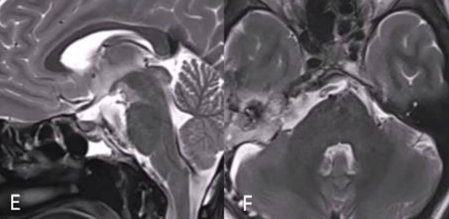

2个月后,进行二次手术,使用右侧mini经岩骨入路切除硬膜内肿瘤。术后MRI显示肿瘤完全切除GTR(图E、F)。术后接受了质子束治疗(PBT)。5个月随访时,她的神经系统检查正常,头面部外观美容效果也好。